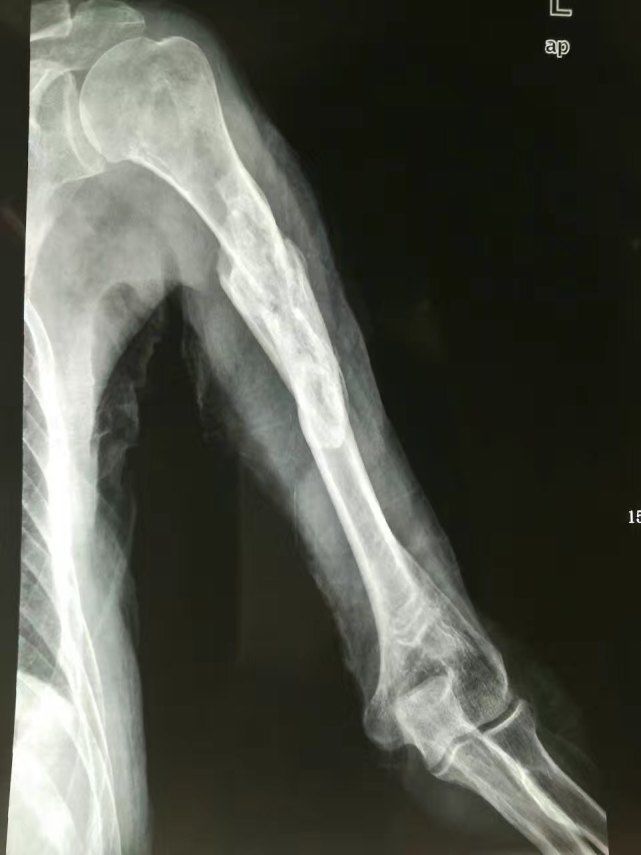

起初大家都以为是桌子裂开了,可是仔细检查之后并没有这个现象,过了一会儿,这位同学的手臂出现了发麻的现象。紧接着疼痛感越来越剧烈,这才大家感觉不对劲,立马将他送去了最近的医院。医生检查确诊他是左臂肱骨骨折,就是因为他在跟同学掰手腕的过程中用力方式不对,用力过猛导致出现的。

医生给他进行了手术,手术过后他需要很长一段时间去康复。其实这件事情在我们的日常生活中是非常常见的,但我们也一定要采取正确的方式方法,千万不要不把它放在心上,毕竟掰手腕造成骨折也是有很多次案例的。年轻人好胜心强,每每提到两个人想要比赛,谁的力量更大的时候,都会采取这样的方式,但是再怎么折腾都一定要保护好自己,千万不要让自己受伤。